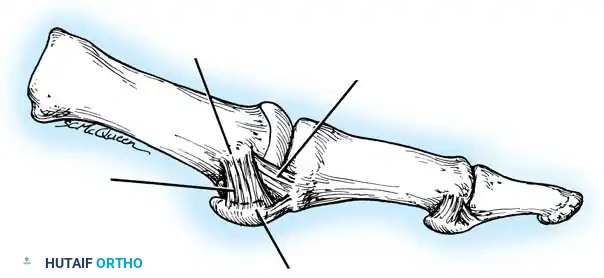

Hallux valgus (lateral deviation of the great toe) is not a single disorder, as the name implies, but a complex deformity of the fi rst ray that frequently is accompanied by deformity and symptoms in the lesser toes (Fig. 78-1). Often the angle between the fi rst and second metatarsals is more than the 8 to 9 degrees usually considered to be the upper limits of normal. The valgus angle of the fi rst metatarsophalangeal joint also is more than the 15 to 20 degrees considered to be the upper limits of normal (Fig. 78-2). If the valgus angle of the fi rst metatarsophalangeal joint exceeds 30 to 35 degrees, pronation of the great toe usually results. With this abnormal rotation, the abductor hallucis, which is normally plantar to the fl exion-extension axis of the fi rst metatarsophalangeal joint, moves further plantarward (Fig. 78-3). In this case, the only restraining medial structure is the medial capsular ligament with its capsulosesamoid portion (inserting into the base of the proximal phalanx) (Fig. 78-4) and capsulophalangeal portion (inserting into the plantar plate). The adductor hallucis, which is unopposed by the abductor hallucis, pulls the great toe further into valgus, stretching the medial capsular ligament (particularly the capsulosesamoid), attenuating this structure, and allowing the metatarsal head to drift medially from the sesamoids. In addition, the fl exor hallucis brevis, fl exor hallucis longus, adductor hallucis, and extensor hallucis longus increase the valgus moment at the metatarsophalangeal joint, further deforming the fi rst ray. The deep transverse intermetatarsal ligament runs between the plantar plates at the metatarsophalangeal joints and does not insert into bone on the adjacent sides of the metatarsal heads. Finally, the sesamoid ridge on the plantar surface of the fi rst metatarsal head (the crista) fl attens because of pressure (abutment) from the tibial sesamoid (Fig. 78-5). With this restraint lost, the fi bular sesamoid displaces partially or completely into the fi rst intermetatarsal space (see Fig. 78-2). In this situation, the patient is bearing less weight on the fi rst ray and more on the lesser metatarsal heads, increasing the likelihood of transfer metatarsalgia, callosities, and stress fracture of a lesser metatarsal.

Fig. 78-4 Anatomy of medial capsular ligament. Note accessory portion of medial capsular ligament inserting into tibial sesamoid and cord portion inserting into base of proximal phalanx plantar to longitudinal axis of fi rst ray. (Redrawn from Haines R, McDougall A: The anatomy of hallux valgus, J Bone Joint Surg 36B:272, 1954.)